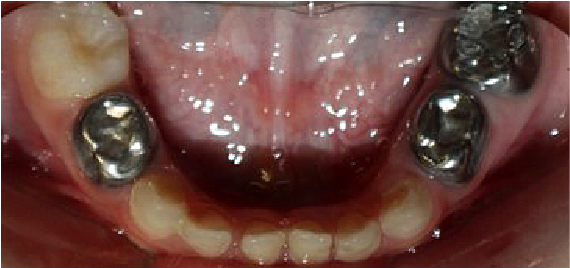

Se llevó a cabo la exploración extraoral y se logró apreciar una ligera asimetría facial, en las fotografías de perfil se ve la implantación de la oreja por debajo de lo normal (figura 1). Al hacer la exploración intraoral se encontraron sobre la superficie de todos los dientes manchas de color amarillento con descalcificaciones y lesiones cavitadas, al complementarse con la historia clínica y antecedentes patológicos, se determinó el diagnóstico de hipoplasia del esmalte generalizada (figura 2).

Figura 2. Examen clínico extraoral.